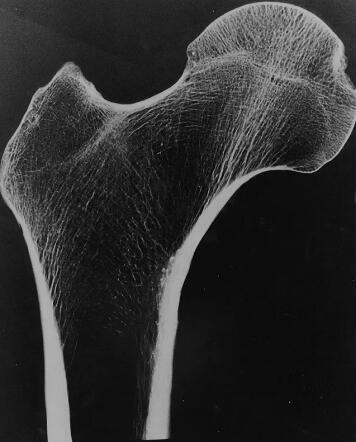

人体骨骼通过小梁的海绵状结构获得耐用性,这种海绵状结构是由相互连接的垂直柱状支撑和水平杆状支撑作为柱和梁组成的网络。小梁越密集骨骼在日常活动中就越有弹性,但是疾病和年龄会影响这种密度。

人类股骨的图像显示出相互连接的白线,这些线构成了小梁结构。

来源:普渡大学